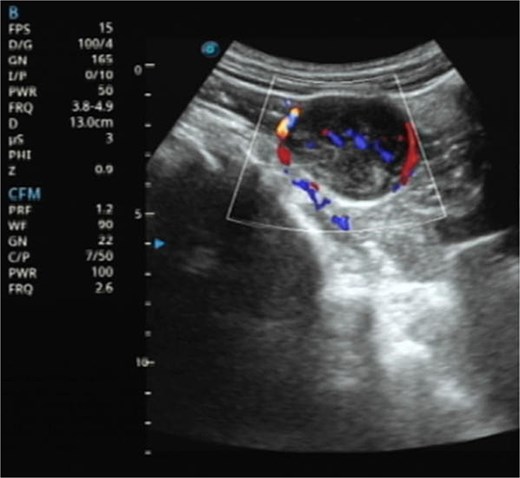

CT imaging shows a pelvic lesion with soft tissue density on non-enhanced scans, marked enhancement of the primary tumor mass after contrast, and coronal/sagittal reconstructions delineating its anatomical location.

Contrast-enhanced CT demonstrated a well-circumscribed, round enhancing mass measuring 4 cm in diameter. Sagittal imaging showed the lesion positioned 0.9 cm from the bladder wall, 4.5 cm from the anterior abdominal wall, and 6.1 cm from the pubic symphysis (Fig. 2). The mass exhibited an intact capsule without evidence of rupture. MRI performed within a 24-hour period, sagittal imaging showed the lesion positioned 7.9 cm from the bladder wall, 1.3 cm from the anterior abdominal wall, and 9.3 cm from the pubic symphysis, and confirmed stable positioning and morphology, maintaining identical spatial relationships to adjacent structures (Fig. 3).